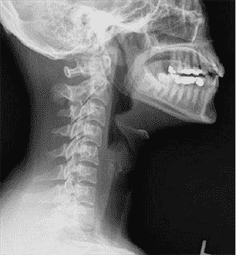

56) A 4-year-old boy is brought into the emergency room by his parents for difficulty in breathing and swallowing. On physical examination the child is febrile, tachycardic, and tachypneic. He is anxious, drooling, and becomes increasingly exhausted while struggling to breathe. A lateral cervical spine radiograph is shown here. Which of the following is the most appropriate management of this patient?

Examine the larynx at bedside

IV antibiotics and admission to the floor

Immediate endotracheal intubation in the emergency room

Immediate endotracheal intubation in the operating room

Immediate tracheostomy in the operating room